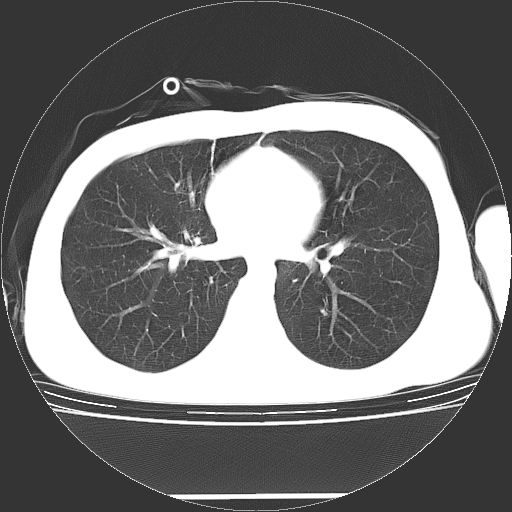

标题: CT19767:男,20岁,右侧气胸行闭式引流术后五天CT检查。 [打印本页]

男,20岁,右侧气胸行闭式引流术后五天ct检查看肺内是否有肺大泡,纵隔窗未见异常,未上传。

1)右侧胸腔闭式引流术后导管留置。2)右肺未见肺大泡。

未见肺大泡,还有微量气体。